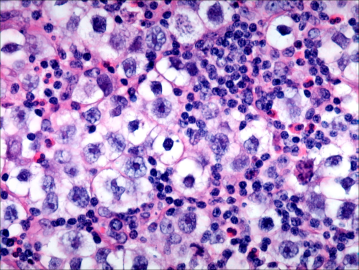

Choriocarcinoma

STGC = syncytiotrophoblastic giant cells